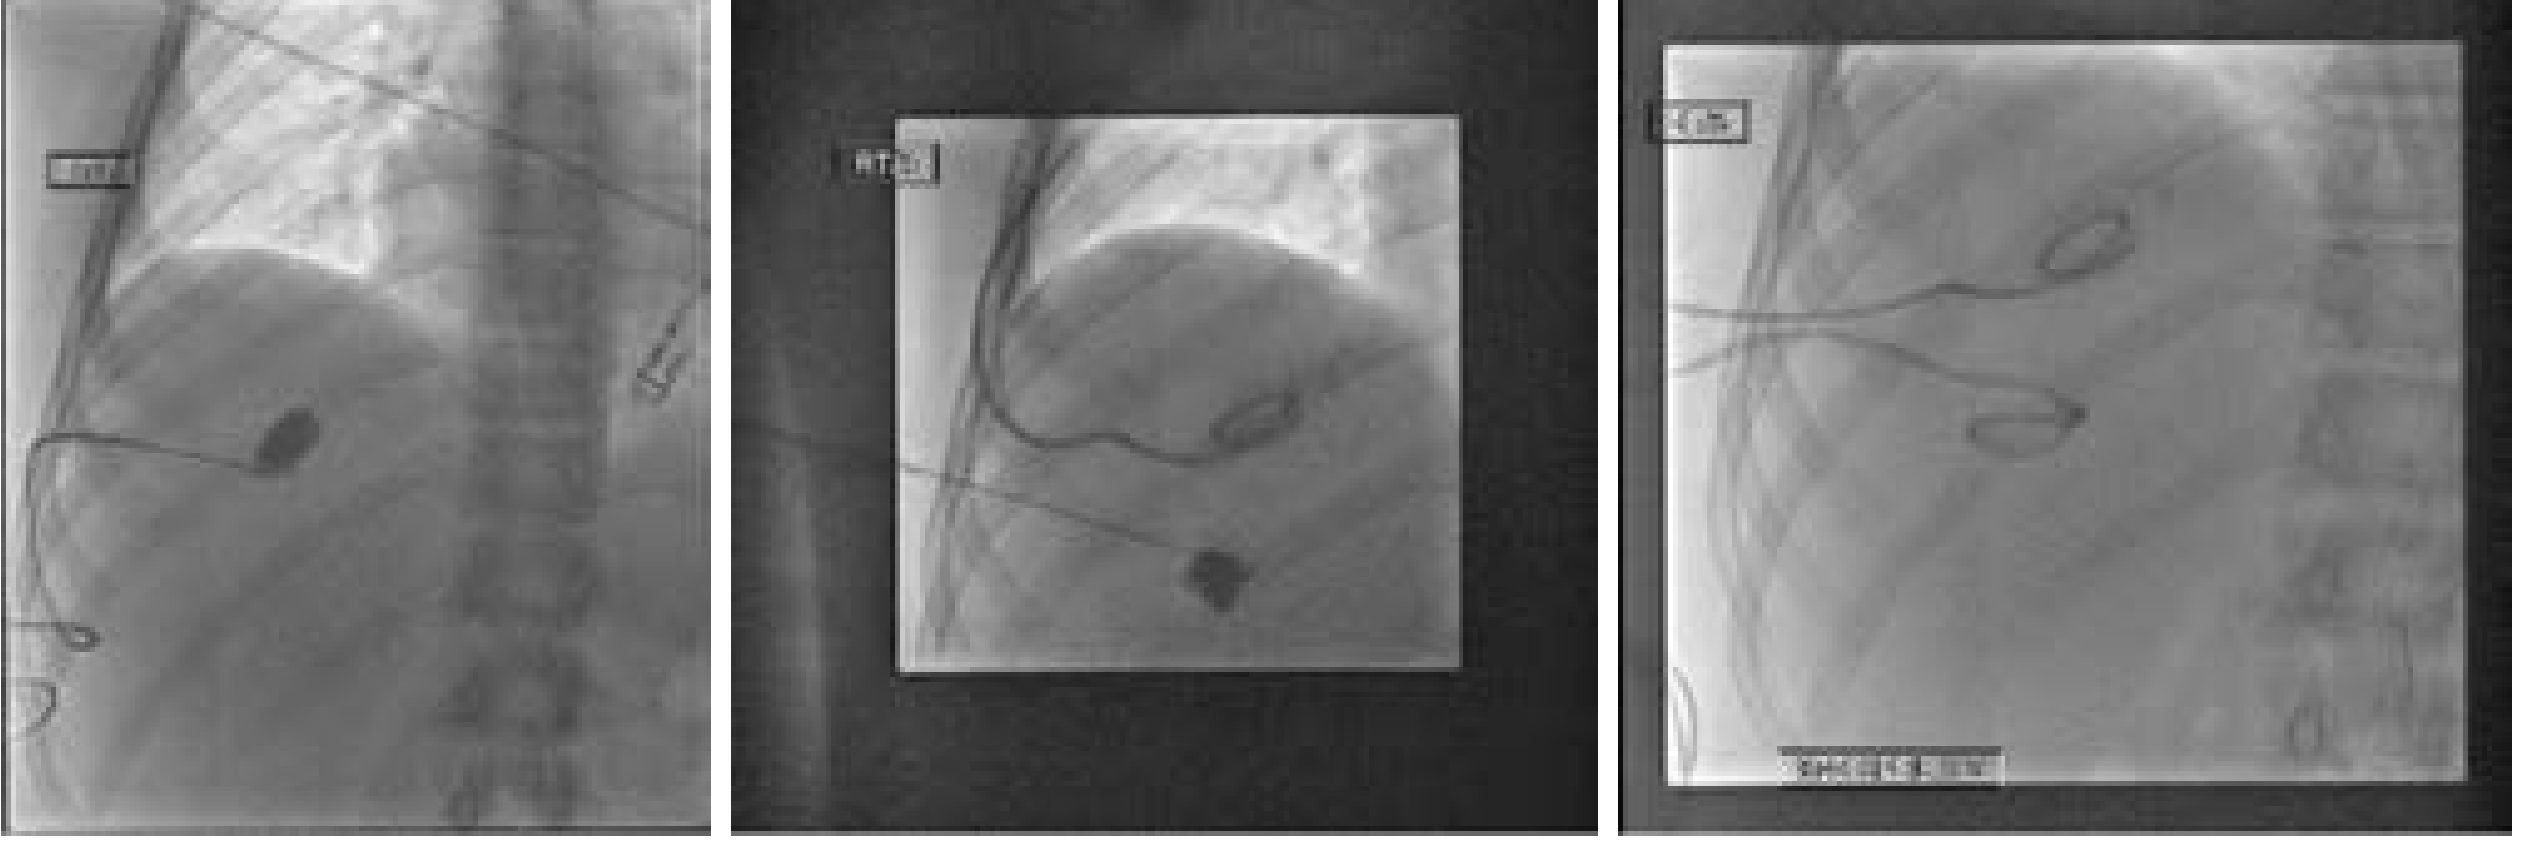

Radiographic images showing drain in place

Radiographic images showing drainage catheter in place — Current Surgical Therapy 14e